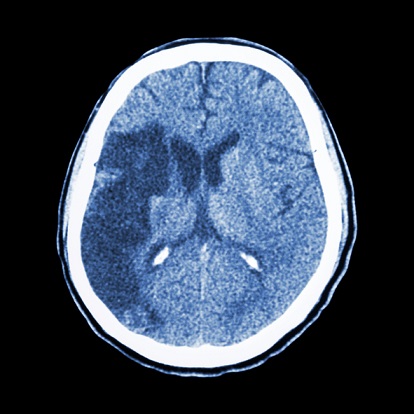

뇌혈류가 차단되면 뇌조직이 허혈성 괴사에 빠짐(회색 부분)

뇌조직은 평상시에도 많은 양의 혈류를 공급받고 있다. 그런데 다양한 원인으로 인하여 뇌혈관에 폐색(혈관 등을 이루는 관이 막히는 경우)이 발생하여 뇌에 공급되는 혈액량이 감소하면 뇌조직이 기능을 제대로 하지 못하게 된다. 뇌혈류 감소가 일정 시간 이상 지속되면 뇌조직의 괴사(조직이나 세포의 일부가 죽는 것)가 시작된다. 뇌조직이 괴사되어 회복 불가능한 상태에 이르렀을 때 이를 뇌경색(cerebral infarction)이라고 한다. 반면 뇌혈류 감소에 의해 뇌기능에 이상이 생겼지만, 적절한 치료를 통해 충분한 뇌혈류가 다시 공급되어 뇌조직의 괴사 없이 뇌기능이 회복되었을 때를 일과성 허혈성 발작(transient ischemic attack)이라고 부른다. 허혈성 뇌졸중은 뇌경색과 일과성 허혈성 발작을 모두 통틀어서 일컫는 용어이다.